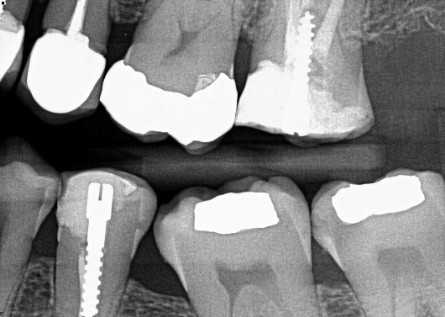

1. (Select ONE OR MORE correct answers)

The radiograph shows evidence of